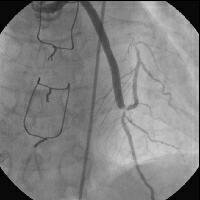

症例は60台前半の男性。18年前にCABG(なぜかLITAはLCX、SVGがLAD)。今回UAPにて入

院。CAGを施行したところSVGのdistalの吻合部からnative LADにかけてのベンツマー

クの90-99%狭窄(SVG to LAD)。SVGのdistalの病変部は血栓様にも見えます。LCAは

LADは起始部でabrupt typeの完全閉塞( LCA)。LCXへのLITAはpatent。